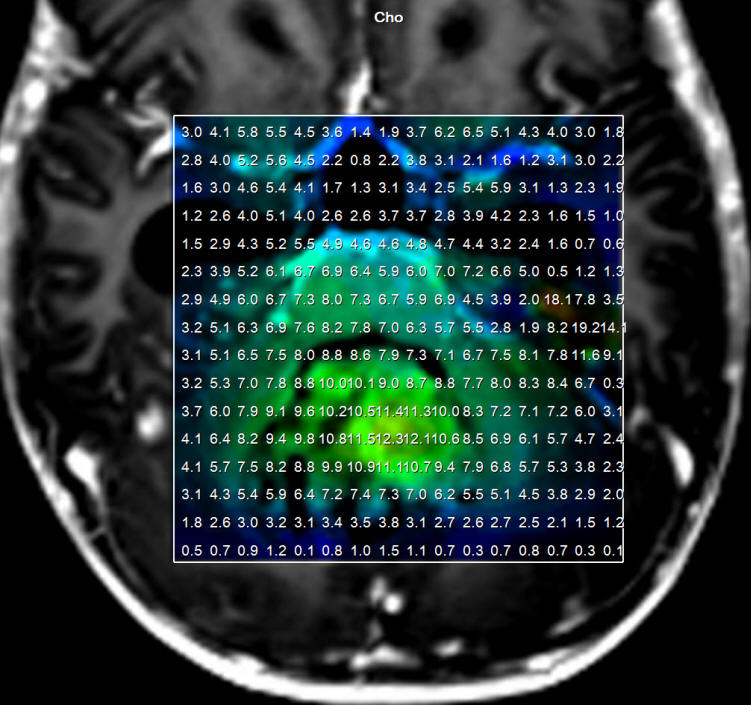

The patient has typical spectroscopic data supporting medulloblastoma. The histologic result will give the answer.

Spectroscopy showing typical data for medulloblastoma

Choline distribution in the medulloblastoma.